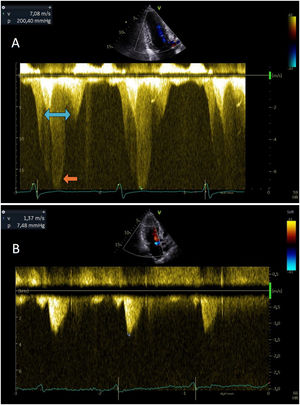

- Miocardiopatía hipertrófica con obstrucción intracavitaria secuencial resuelta con mavacamten

- Margarida G. Figueiredo, José Miguel Viegas, Sílvia Aguiar Rosa

- Rev Esp Cardiol. 2026;79:187-8